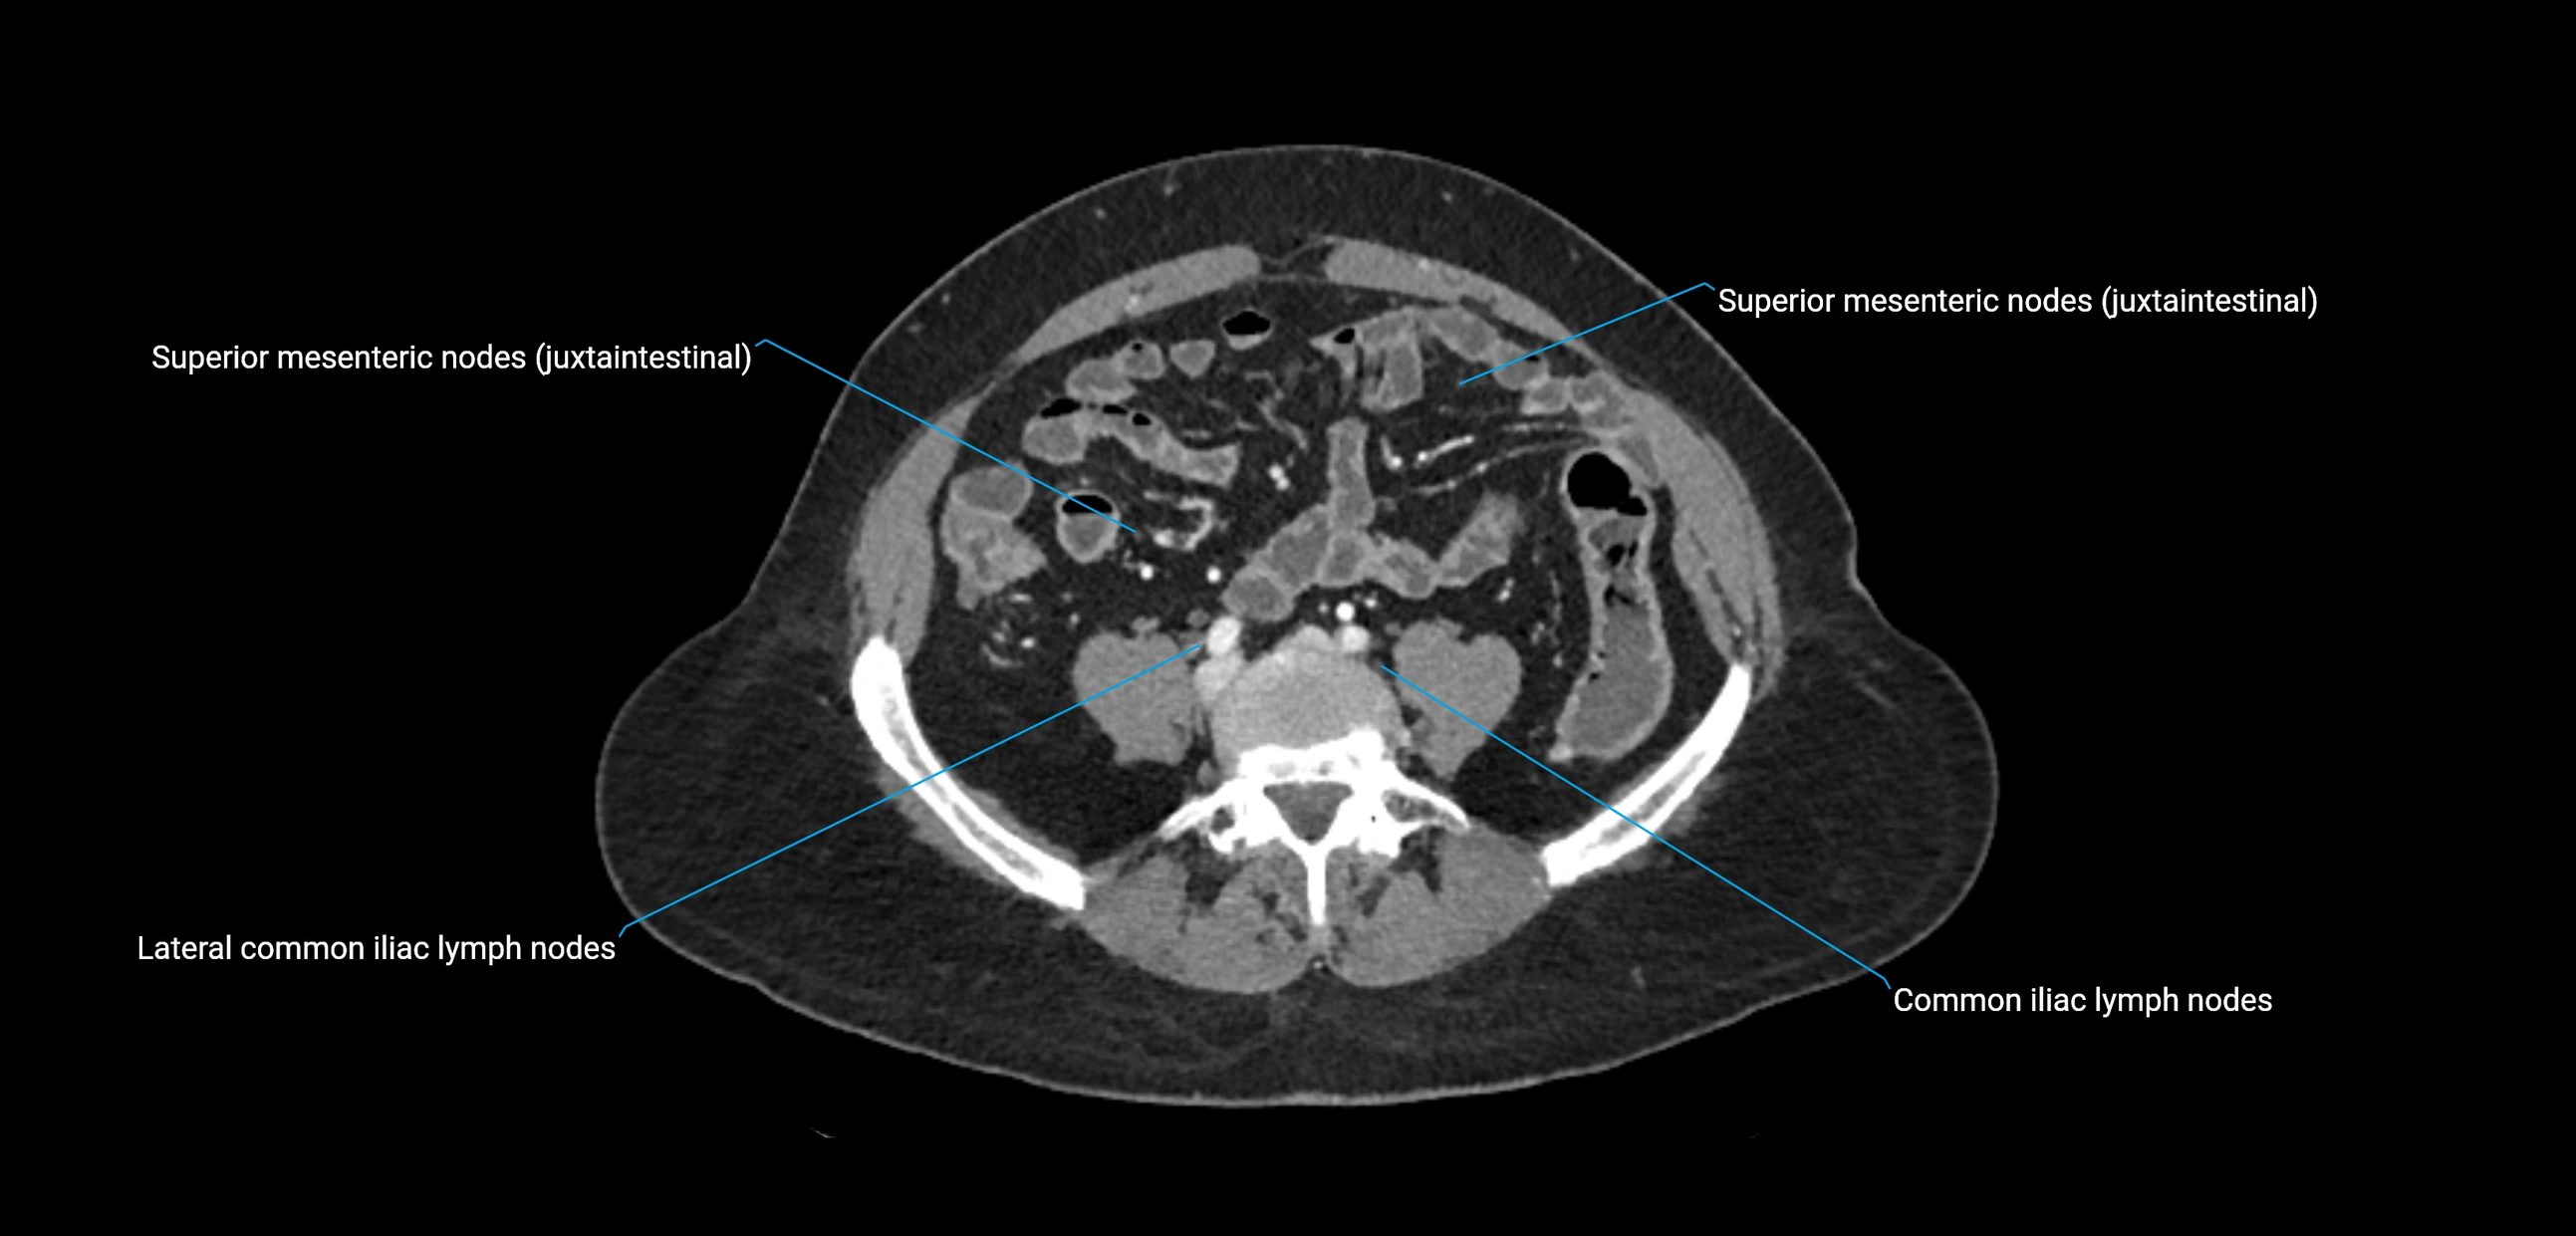

The lateral aortic lymph nodes (also called para-aortic lymph nodes) are a major group of retroperitoneal lymph nodes located along the abdominal aorta and its branches. They lie between the diaphragmatic crura superiorly and the bifurcation of the aorta at L4 inferiorly.

They are positioned on both sides of the abdominal aorta:

• Right lateral aortic nodes: adjacent to the inferior vena cava (IVC)

• Left lateral aortic nodes: lateral to the abdominal aorta

These nodes receive lymph from a wide range of abdominal and pelvic structures. Specifically, they drain lymph from the kidneys, suprarenal glands, gonads (testes/ovaries), uterus, uterine tubes, and pelvic organs, before converging into the lumbar lymphatic trunks, which terminate in the cisterna chyli → thoracic duct.

Clinically, the lateral aortic lymph nodes are critically important in oncology, being involved in the spread of testicular cancer, ovarian cancer, endometrial cancer, cervical cancer, renal malignancies, and retroperitoneal lymphomas. They are also key targets in retroperitoneal lymph node dissection (RPLND) for testicular tumors.